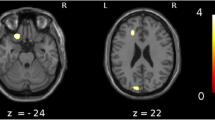

The results of the statistical image analysis in this study are shown in Fig. 1 and Table 2. The GM volume in the bilateral medial frontal lobes and bilateral medial temporal lobes was positively correlated with MMSE scores (Fig. 1a, Table 2). Furthermore, there was a positive correlation between rCBF and MMSE scores in the medial temporal lobes, including the hippocampus and parahippocampal gyrus, posterior and anterior cingulate gyrus, inferior temporal lobe, and basal frontal area (Fig. 1b, Table 2).

Areas of significant correlations with Mini-Mental State Examination (MMSE) scores or pareidolia scores in dementia with Lewy bodies (DLB) patients. a Areas of significant correlation between gray matter volume and MMSE scores in patients with DLB are shown (p < 0.001, uncorrected). The bilateral medial frontal lobes and bilateral medial temporal lobes are highlighted (p < 0.001, uncorrected). b Areas of significant correlation between regional cerebral blood flow (rCBF) and MMSE score in DLB patients are shown (p < 0.001, uncorrected). The bilateral medial temporal lobes, posterior and cingulate gyri, inferior temporal lobe, and basal frontal area are highlighted as significantly correlated areas. c Areas of significant correlation between rCBF and pareidolia scores in DLB patients are shown (p < 0.001, uncorrected). The bilateral frontal and cingulate gyri, left posterior cingulate gyrus, and left parietal cortex are highlighted as significantly correlated areas

There were no significant correlations between regional GM and noise pareidolia scores nor between rCBF and noise pareidolia scores in 40 patients with visual hallucinations; then we performed the analysis in the whole 147 patients. Analysis of the correlation between GM and noise pareidolia scores revealed no significant areas; however, rCBF and noise pareidolia scores were weakly correlated in the bilateral frontal and cingulate gyri (Brodmann area [BA]8 and BA9), left posterior cingulate gyrus (BA31), and left parietal cortex (BA39 and BA40). In contrast, there was no significant correlation between the occipital CBF and noise pareidolia scores (Fig. 1c, Table 3). In 40 DLB patients with hallucinations, there was no significant difference in the correlation between occipital CBF and noise pareidolia scores (positive scores or negative scores) in noise pareidolia tests.